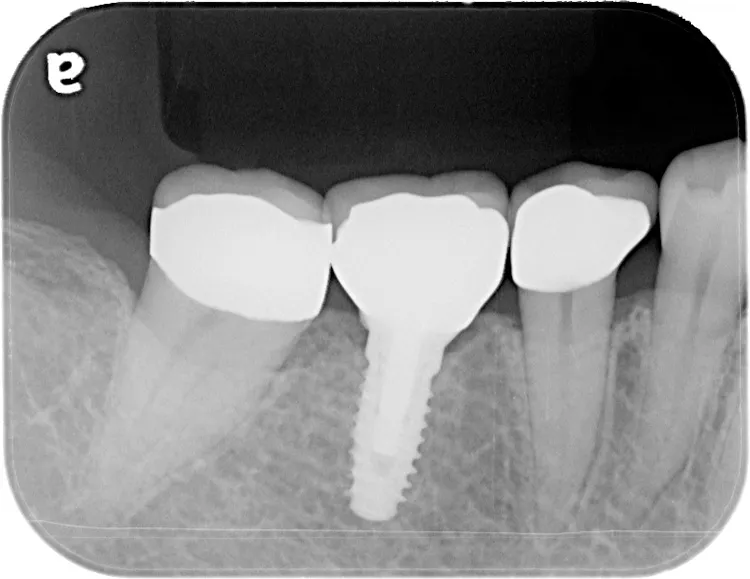

第一大臼歯1歯欠損をインプラントで回復したケースです。第一大臼歯は永久歯の中で一番最初に生える歯ですが、一番早く傷んでしまう歯でもあります。噛む力の60%を負担し噛み合わせの安定に大きく影響しますので、この歯が欠損すると噛み合わせに悪い影響を与えてしまいます。インプラントで治すことにより噛み合わせが安定するだけでなく、ブリッジのように隣在歯を削らないので天然歯の寿命を延ばすメリットもあります。

左下67 欠損に対してインプラント治療を行った症例

部分床義歯を使用していたが、どうしても慣れない上にしっかり噛むことができないためインプラント治療を希望